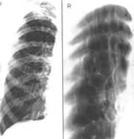

麻疹病毒肺炎麻疹病毒肺炎X片

其他輔助檢查:胸部X線檢查,麻疹病毒肺炎表現為瀰漫性細支氣管和肺間質炎症改變,肺紋理性細菌感染的炎症浸潤常為肺段分布的支氣管肺炎,多位於一側或雙側肺部的下葉。